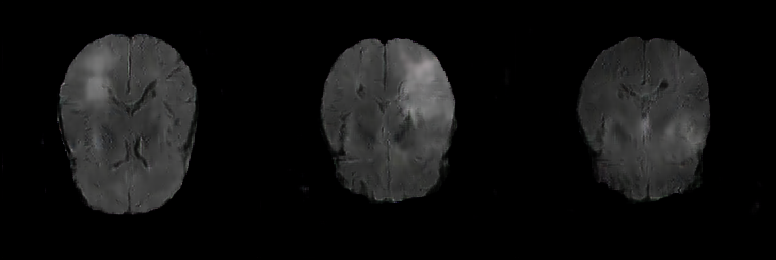

It can be seen from Figure 1 that the same organization is displayed differently in different modalities [22]. The brain tissue is relatively constant in the T1 and T2. The edema area is dark in the T1 modal, while the white shadow area is formed on the T2. The T1 pays more attention to the anatomical details of each tissue; The T2 can highlight the lesion area more clearly and retain a high signal to the cerebrospinal fluid [23]. FLAIR uses water suppression technology for imaging. Free water is a low signal (edema state), and bound water is a high signal (non-edema area) [22]. The FLAIR sequence can clearly show the lesions near the ventricle or near the cortex [24]. That is useful for observation in the diagnosis of diseases such as gliomas. Therefore, this work mainly focuses on the FLAIR sequence generation of gliomas images.

This research exploits the BRATS 2019 training dataset containing 259 High-Grade Gliomas (HGG) cases. We select the 64th slice among the whole 155 slices as the initial/final slices will convey a negligible amount of information and affect the training [32]. Therefore, the training dataset is 259 FLAIR brain axial (AXI) MR images, zero-padded to 256 x 256 from original-sized 240 x 240 pixels for better GAN training. Figure 4 shows real FLAIR samples.